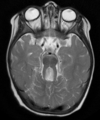

19

Q

A

Cisto epidermóide do SNC

Sinal heterogêneo no FLAIR e Hipersinal na DWI

Extra-axial nas sisternas da base.